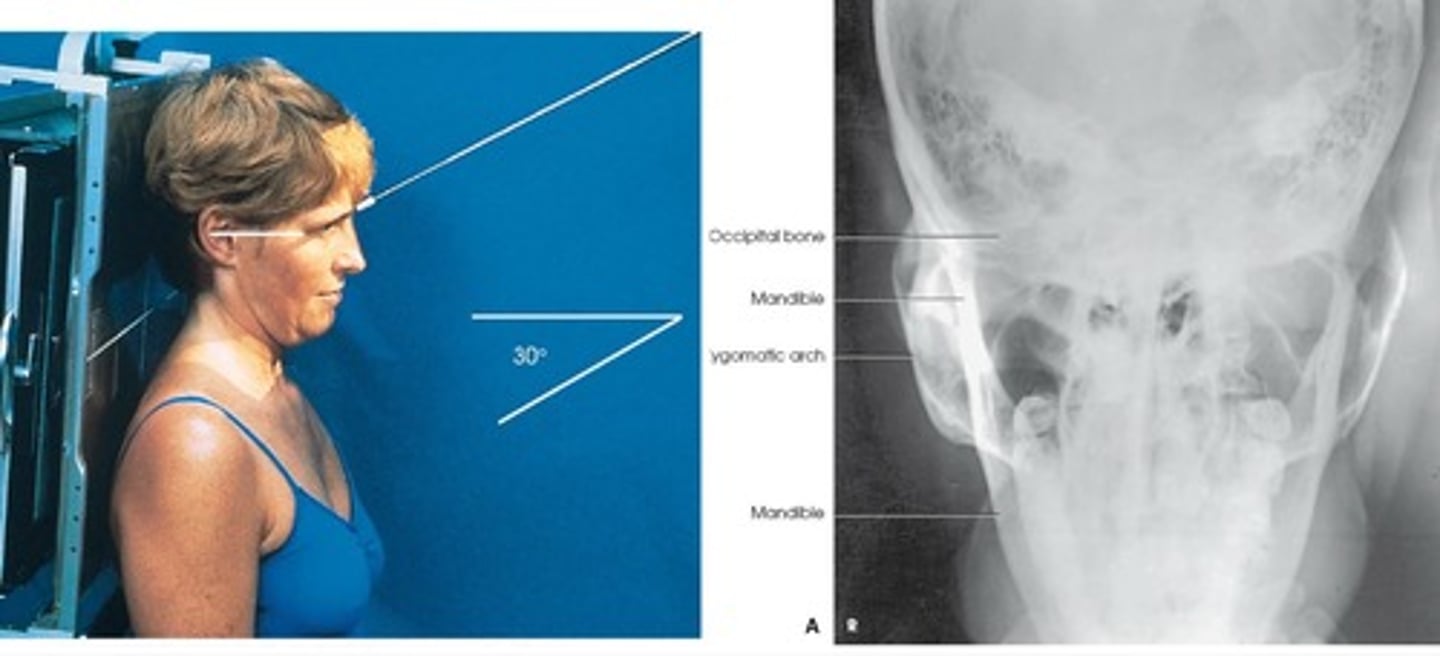

AP Axial (modified Townes Method)

- PT supine/ chin tucked so OML is per to the IR

- 30 deg caudad, entering at the glabella .

- Symmetric AP axial projection of both arches free of superimposition (lateral to mandibular rami)

What is this projection?

How is Patient positing?

What is the CR?

What are the structures shown?